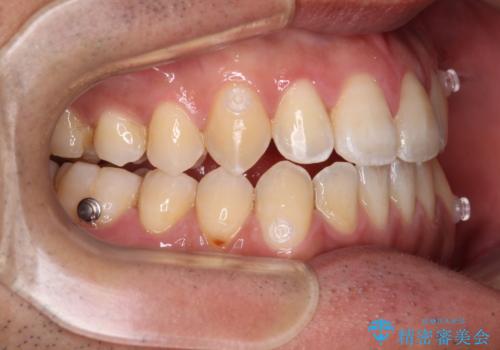

- 前歯のデコボコを気にして来院された患者様です。

歯列としてはワイヤー装置でもインビザラインでも対応可能でしたが、インビザラインが苦手とする上顎側切歯(真ん中から2番目の歯)の舌側転位が顕著でした。

治療の確実性を上げるために、インビザライン開始前に上顎のワイヤー装置にて舌側転位を解消し、その後インビザラインにて矯正治療を行うこととしました。

前歯のデコボコが早めに改善され、スムーズに治療を終えることができました。